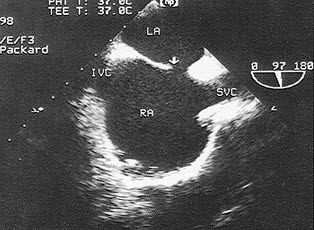

51、单项选择题

该食管超声心动图显示图像为()

A.房间隔缺损(上腔型)

B.房间隔缺损(下腔型)

C.房间隔缺损(中央型)

D.房间隔缺损(混合型)

E.冠状静脉窦扩张